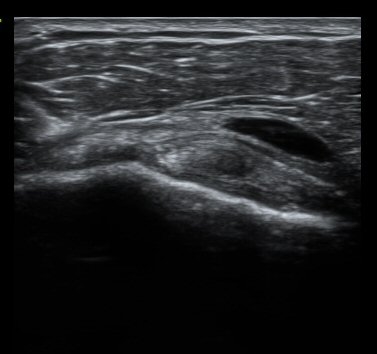

ȸÀü±Ù°³°£°Ý Ⱦ´Ü¸é°Ë»ç¿¡¼­ Á¡¾×³¶³» ¼ö¾×Àú·ù°¡ °üÂûµÈ´Ù(±×¸² 1). ÀÌµÎ¹Ú±Ù°Ç °í¶û¿¡¼­´Â ƯÀÌ ¼Ò°ßÀ» º¸ÀÌÁö ¾Ê´Â´Ù(±×¸² 2). ȸÀü±Ù°³°£°Ý ³»Ãø¿¡¼­ °ß°©ÇϱٰÇÀÇ ÆÄ¿­°ú Á¡¾×³¶³» ¼ö¾×Àú·ù°¡ °üÂûµÈ´Ù(±×¸² 3, 4). ±Ø»ó°Ç Ⱦ´Ü